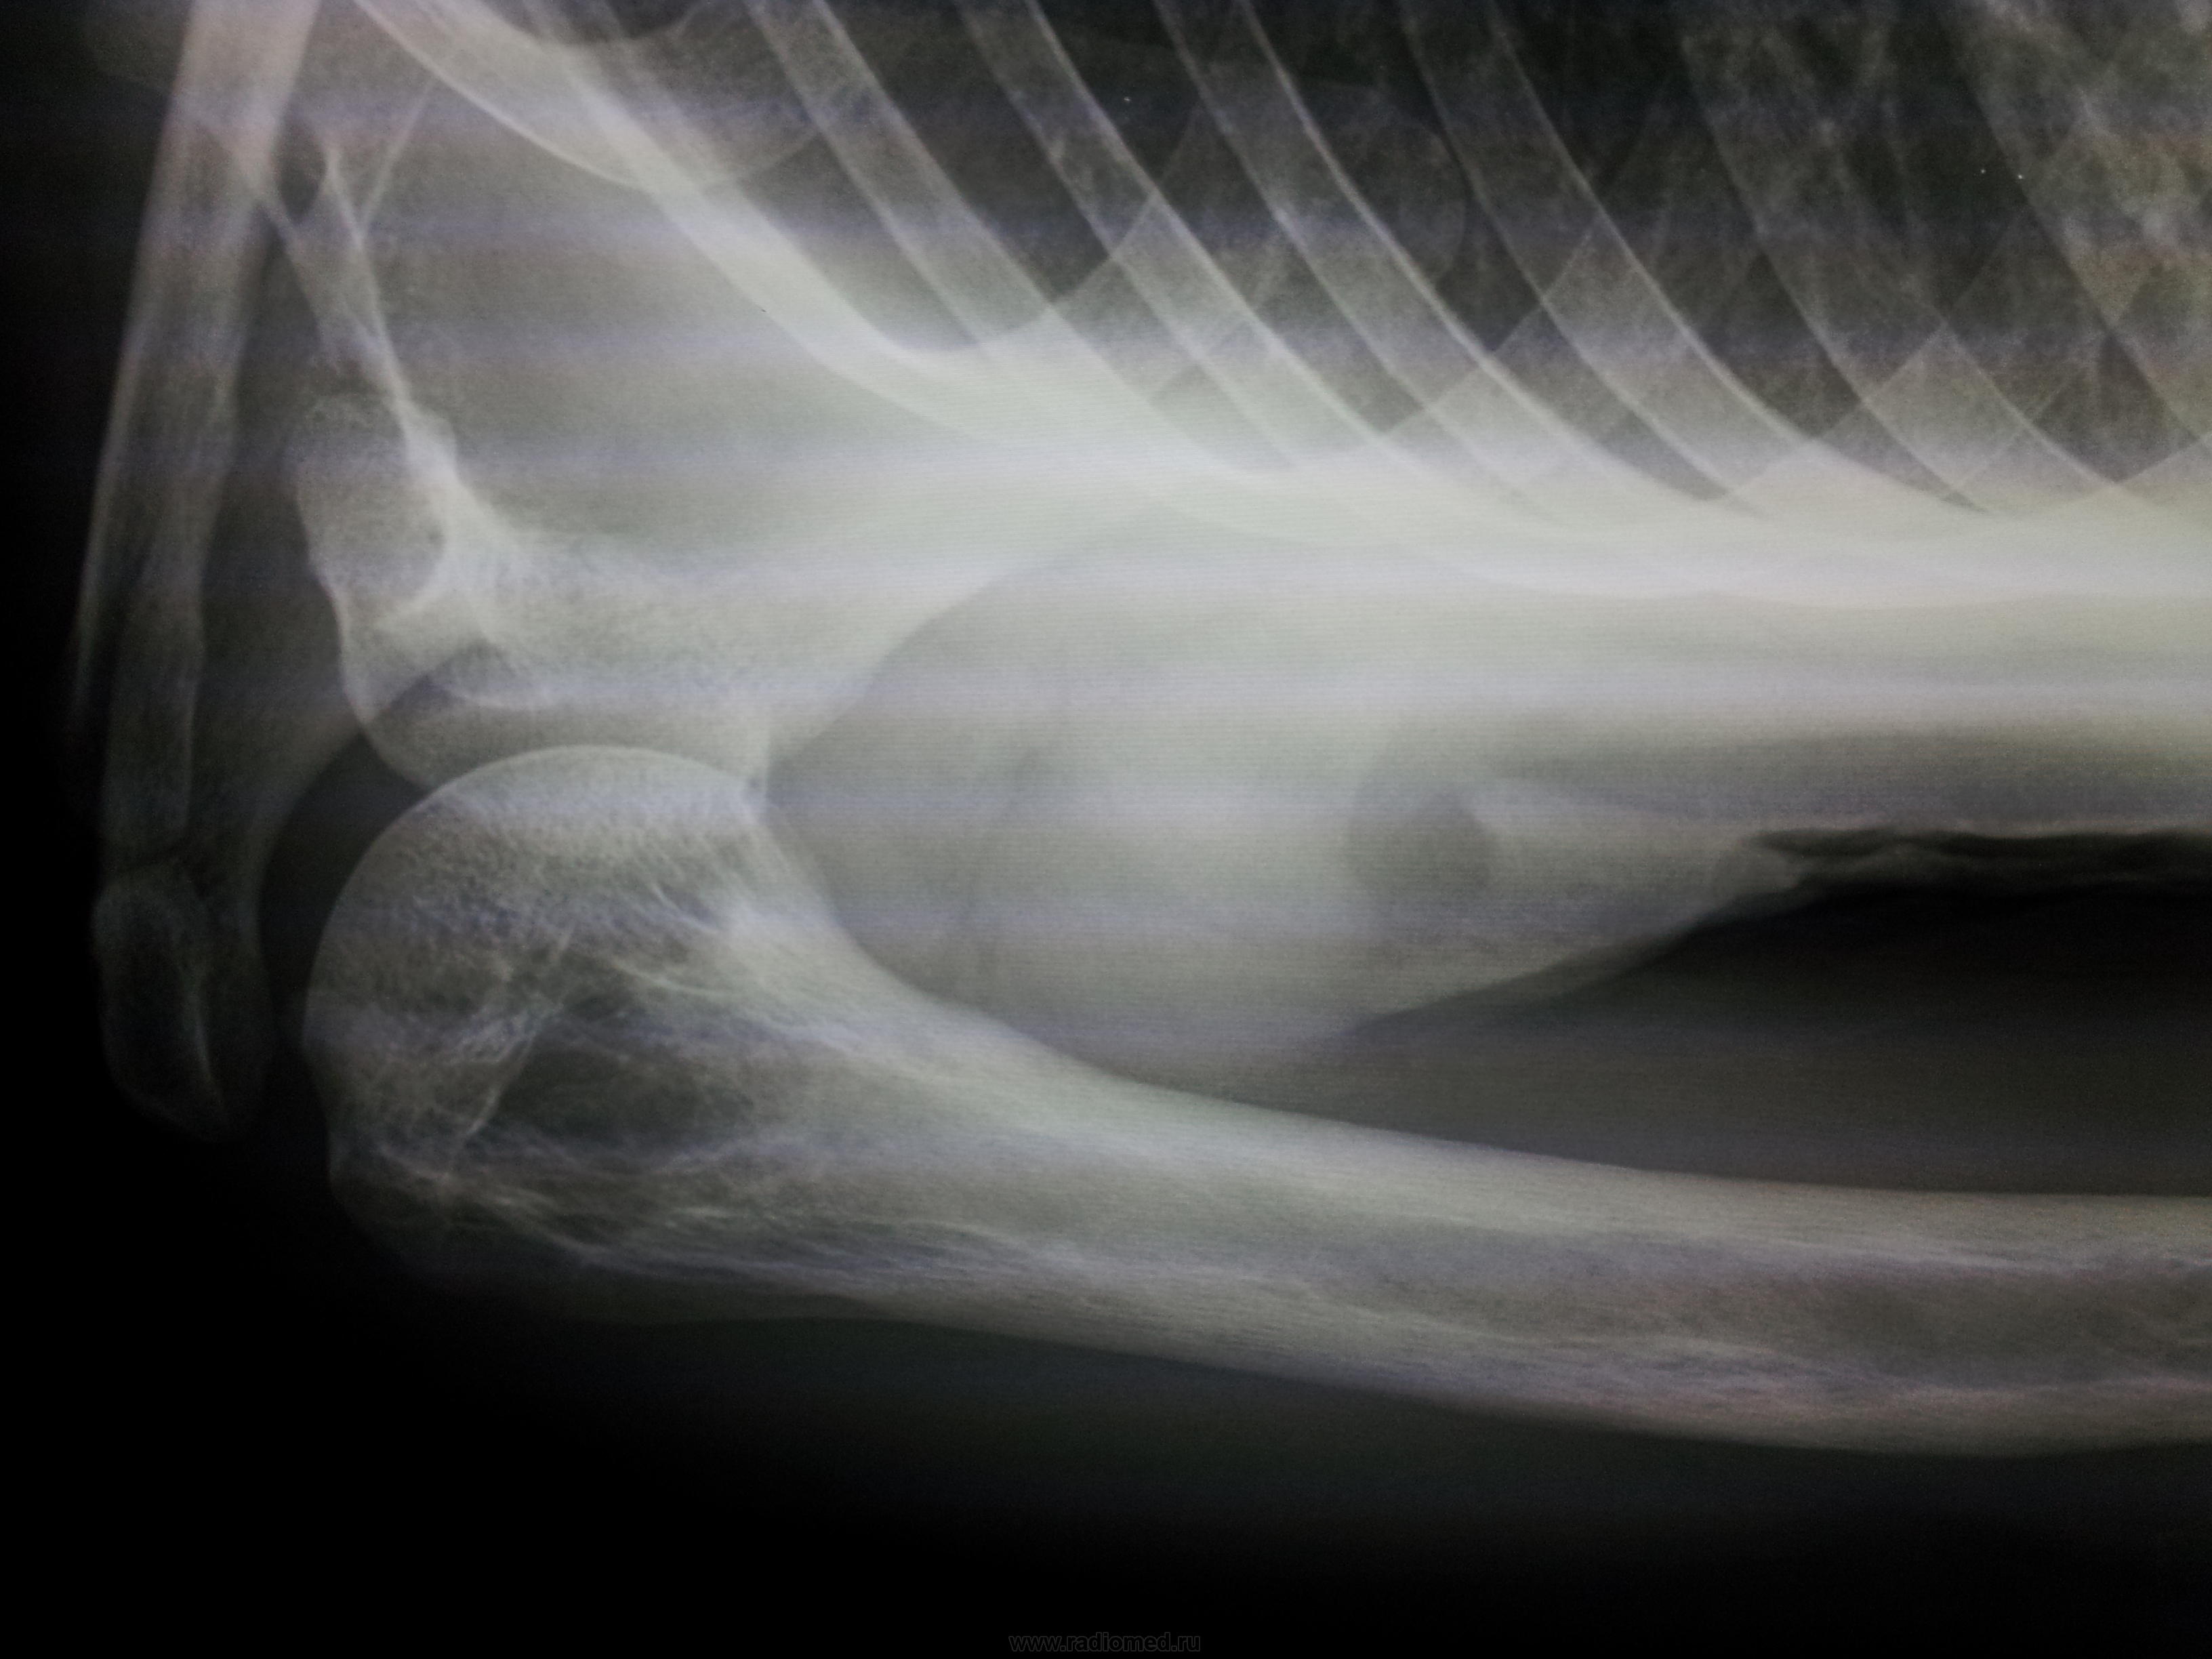

Есть участок обызвествления связки продольной мышцы. Перестройка в плечевой кости тоже есть. Но какая она? У пожилых может быть и добракачественная, гемангиомоподобная. Не знаю ваших возможностей дообследования. Есть возможность - отправьте на МРТ (в любом случае не помешает), нет возможности, сделайте другой сустав.

Mne struktura kosti ne nravitsa .A jalobi na bol v sustave.Mujcine 72 qoda .

Настораживает необычная перестройка кортикального слоя всего диафиза плеча - утолщение и разволокнение - нет ли здесь болезни Пэджета?